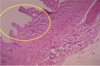

Hypertrophic Cardiomyopathy

Marked LV hypertrophy w/ asymmetric bulging of large interventricular septum into LV

50% familial, though a variety of different genes may be responsible for the disease

Hypertrophic Cardiomyopathy

Narrowing of outflow tract before aortic valve - subaortic stenosis

Hypertrophic Cardiomyopathy

Hypertrophic Cardiomyopathy

Myocardial disarray, not arranged parallel

Usually happens in fit, young adults and results fatally

Hypertrophic cardiomyopathy

Myocardial disarray (not arranged in parallel)

Hypertrophic Cardiomyopathy